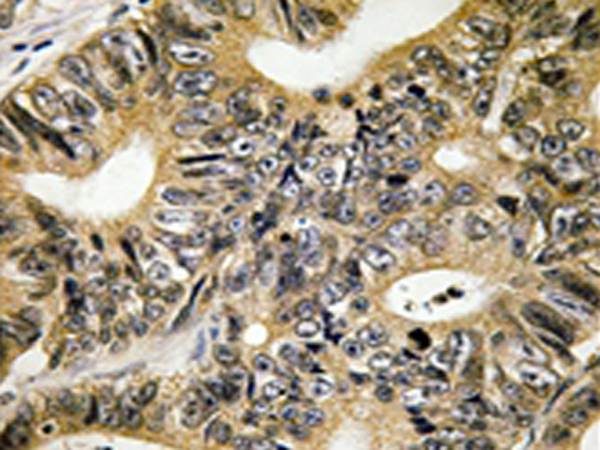

IHC positive control: |

Human colon carcinoma tissue |